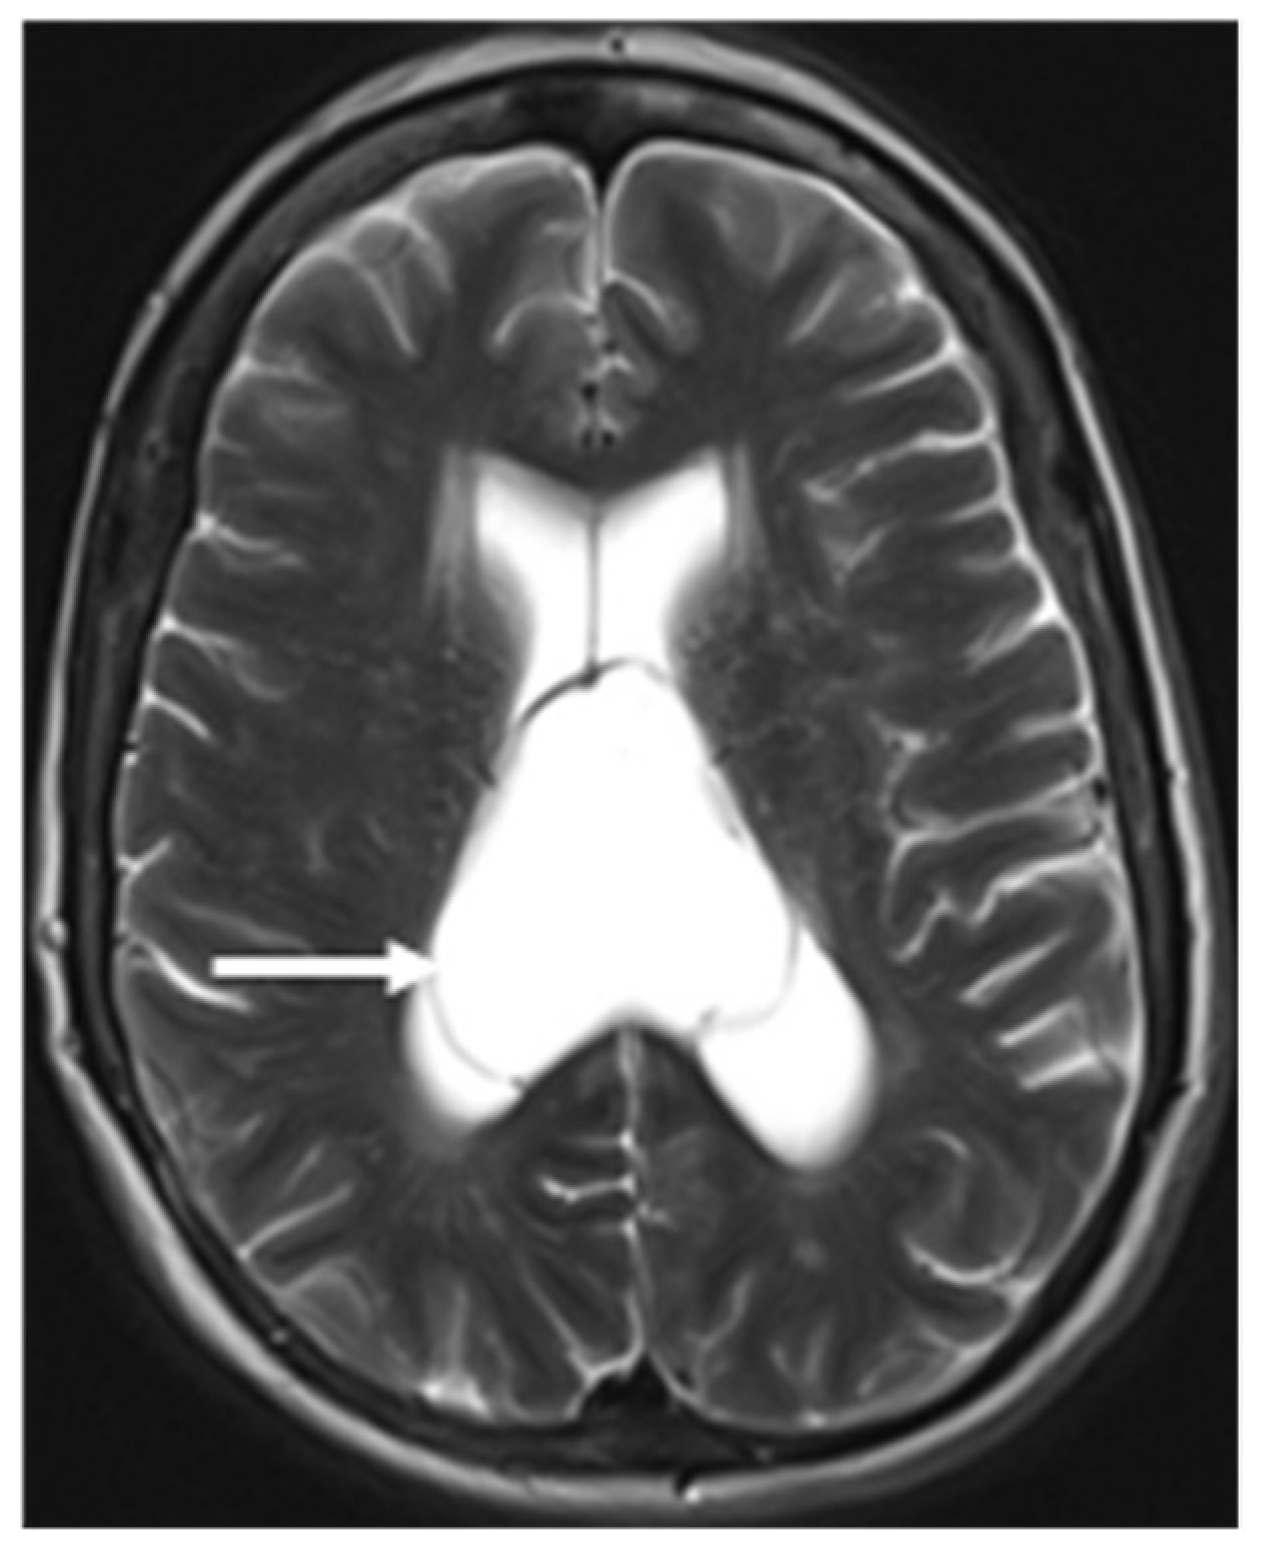

The development of the SP begins early intrauterine life with the development of the fetal brain. During the first trimester of pregnancy, the SP arises due to the folding and growth of the neural tissue in the midline. By the latter part of the first trimester or beginning of the second trimester of pregnancy, it consists of two parallel sheets which project downward from the roof of the developing brain to form a fluid-filled pocket-like closed vertically oriented compartment called CSP. The CSP becomes visible ultrasonographically from the second trimester and obliterates between 36 and 40 weeks of gestation. Based on cranial ultrasonography, Mott et al. demonstrated that CSP is detected in all normal infants under 36 weeks of gestational age. They further described the prevalence of CSP at 36, 38, and 40 weeks of gestation, in about 69%, 54%, and 36% of foetuses, respectively (4).Two leaflets gradually fuse each other, starting anteriorly and progressing posteriorly to obliterate the cavity, resulting in a fully formed septum pellucidum. This fusion occasionally delays up to 24 months after birth and in some individuals, it may persist throughout adult life. These midline intracranial cysts are more common than expected due to frequent detection using CT and MRI brains up to 72 % in healthy adults (5) (Figure 3a-c).The boundaries of CSP are described in Table 2 (6).

The MR/CT findings of the SP and its variations are straightforward and represented by the presence of a fluid-filled cavity between the two leaflets of the SP. Therefore, this will follow CSF signal intensity in all the MRI sequences. This is characterised by low signal intensity on T1W, high signal intensity on T2W and suppression of signal in FLAIR sequences. The rapid advancement of in utero magnetic resonance (iuMR) imaging techniques has increased the prenatal detection of abnormalities in the corpus callosum, such as the absence of the corpus callosum, a narrow or wide corpus callosum, and abnormal shape of the corpus callosum (17).After conducting a study on 200 iuMR in foetuses ranging from 18 to 37 weeks of gestational age, Javis et al. concluded that the CSPV length constantly increased throughout pregnancy. This increase likely implies the rapid expansion of the cerebral hemispheres during the second and third trimesters. On the other hand, the width and volume of the CSPV peaked between 29 and 31 weeks of gestational age and subsequently decreased during the later stages of pregnancy. They further stated that the width of the cavum septi pellucidi is larger than the width of the cavum vergae at each stage of gestation. Born et al. studied three age groups involving 151 healthy subjects. The study revealed that the length of the SP was measured to be 28 ± 6.9 mm in children, 35 ± 7.3 mm in young adults, and 37 ± 5.0 mm in elderly adults (mean ± SD) (18).Tsutsumi et al. applied the Coronal Interference Steady State (CISS) sequence, a gradient-echo MR imaging technique, to precisely delineate a wide range of pathologies. This method proves valuable when standard MR imaging sequences fail to provide adequate anatomical details and enhanced sensitivity in diagnosing conditions such as CSP, CV, and CVI (19).

Figure 3a-c. (a) Axial non-contrast CT brain shows CSP (long arrow), and (b) axial (C) coronal T2W MRI brain shows small CSP (short arrow).